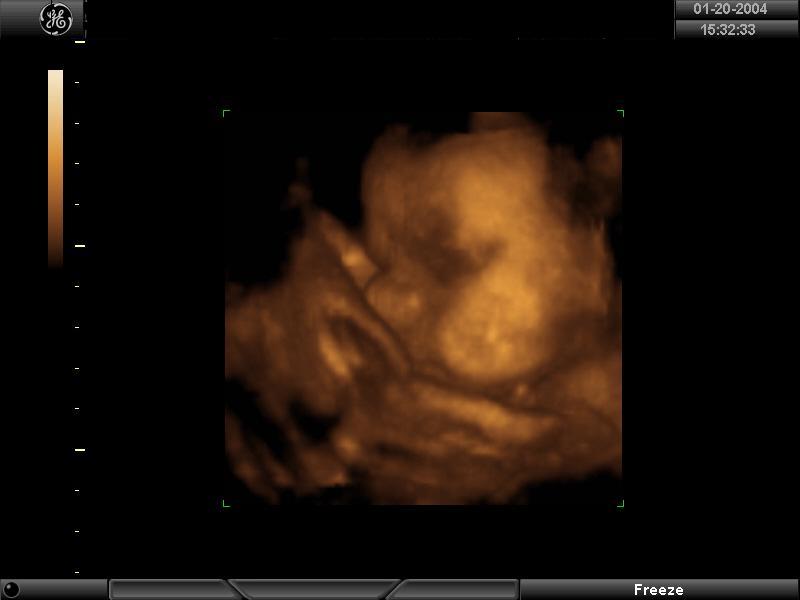

1/20/04

One of the things I've really looked forward to was the 4-D ultrasound. It's 4-D because not only does it show the baby in 3-D, but there is movement, too. Today was my 29 week appointment and (at last!) the day of the super-tech portraits!!

The sonographer had a hard time getting him to move his face directly toward us. The entire time, either his cord was in the way or his hand (and sometimes his foot) was in his face. So the pictures are mostly profiles, but I was still excited to see that. The doctor, though, thought I might be able to get a good front facial view at my next appointment, so he rescheduled me in two weeks for a re-do at no charge! I can't complain about that!!

Before the ultrasound, I ate some cookies and drank some apple juice hoping to see the baby in action, but as it turned out, it was better for him just to be still so he could have his picture made for the first time. Like last time, we got a VHS of the regular sonogram, plus this time included a CD-R of the still portraits and some black and white print-outs. I've included two of my favorite shots below, in both black and white and in the "gold tone." She said these pictures don't show hair, but I don't know. . .